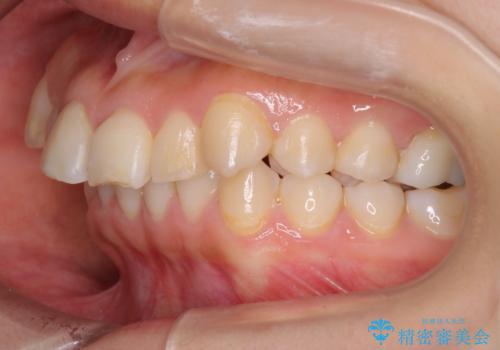

【ワイヤー矯正】前歯が出てるのをなおしたい。

- 前歯の凸凹を主訴に来院されました。

見た目だけではなくかみ合わせも良くなったと満足して頂きました。

治療後は見た目だけでなく、噛みやすくなったと満足していただけました。